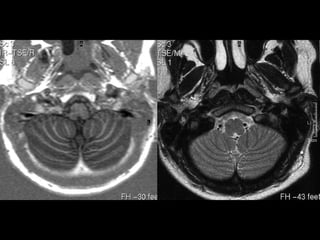

MESENCÉFALO

COLÍCULOS

SUPERIORES

INFERIORES

• TETO MESENCEFÁLICO (LÂMINA QUADRIGEMINAL)

• PEDÚNCULOS CEREBELARES SUPERIORES E

• IV VENTRÍCULO

• CEREBELO - HEMISFÉRIOS

PONTE / BULBO

CEREBELO

VERMIS

TONSILAS

NÚCLEO

DENTADO

HEMISFÉRIO

CEREBELAR